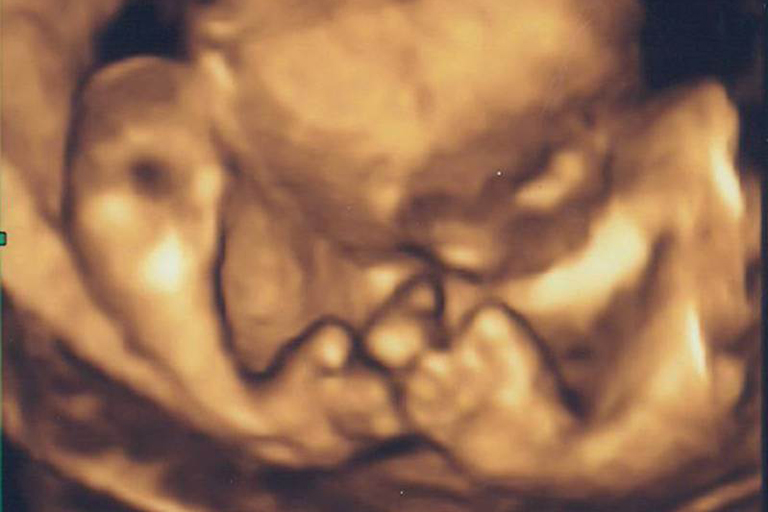

Schon während der Schwangerschaft lassen sich mittels Ultraschalluntersuchung Fehlbildungen, wie z. B. ein Klumpfuß am Baby erkennen. Dies ist auch beim erblich bedingten Klumpfuß möglich.

Allerdings ist diese Untersuchung relativ ungenau. D. h. es können falsch positive Ergebnisse entstehen – ein Klumpfuß wird am ungeborenen Kind diagnostiziert, dieser ist aber nicht vorhanden. In der Literatur wird die Treffsicherheit einer solchen Untersuchung zwischen 71 und 83 % angegeben. Die Wahrscheinlichkeit für ein falsch positives Ergebnis in der Ultraschalluntersuchung liegt zwischen 17 und 29 % bei einseitig betroffenen Kindern. Bei doppelseitigem Klumpfuß ist diese Rate deutlich niedriger (7 %).